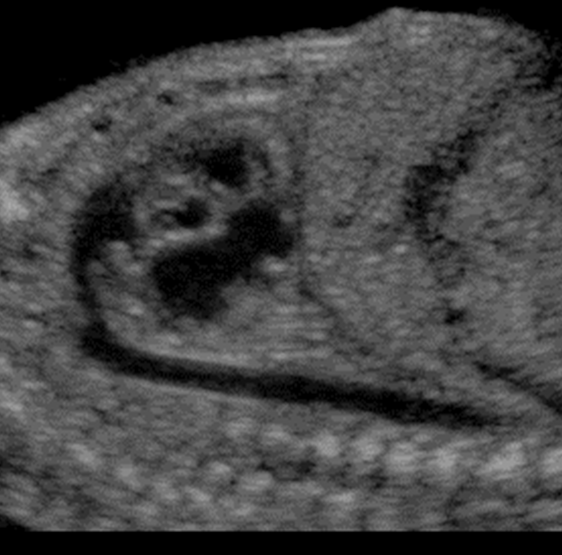

What view is this?

5 chamber view (used to recored aortic root, outflow, LVOT)